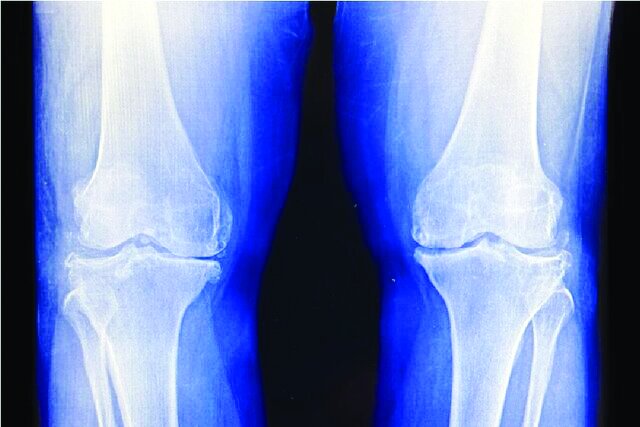

برای افرادی که مبتلا به آرتروز پیشرفته(OA) زانو و درد شدید، تورم و کاهش شدید عملکرد همراه با آن هستند، نقطه پایانی، اغلب جراحی تعویض مفصل زانو است. بنابراین رویکردهای جایگزینی که درد را کاهش دهند و در عین حال عملکرد را بهبود بخشند و جراحی را به تأخیر بیندازند، مورد استقبال قرار میگیرند.

به نقل از نیو اطلس، نتایج یک کارآزمایی بالینی جدید به رهبری کالج پزشکی دانشگاه ملی سئول که در نشست سالانه انجمن آمریکایی انکولوژی پرتودرمانی(ASTRO) ارائه شد، نشان داده است که چگونه یک دوره پرتودرمانی با دوز پایین میتواند درد را تسکین داده و عملکرد را در افراد مبتلا به آرتروز خفیف تا متوسط زانو بهبود بخشد.

دکتر بیونگ هیوک کیم(Byoung Hyuck Kim)، محقق اصلی این آزمایش و استادیار انکولوژی پرتودرمانی در مرکز پزشکی بورامائه(Boramae) دانشگاه ملی سئول گفت: افراد مبتلا به آرتروز دردناک زانو اغلب با انتخاب دشواری بین خطرات عوارض جانبی داروهای مسکن و خطرات جراحی تعویض مفصل مواجه هستند. بنابراین نیاز بالینی به مداخلات متوسط بین داروهای مسکن ضعیف و جراحی تهاجمی وجود دارد و ما فکر میکنیم پرتودرمانی ممکن است گزینه مناسبی برای این بیماران باشد، به خصوص زمانی که داروها و تزریقات به خوبی تحمل نمیشوند. چکیده این مطالعه در وبسایت نشست سالانه ASTRO ۲۰۲۵ موجود است.

دانشمندان میگویند پرتودرمانی با دوز پایین، درد آرتروز زانو را تسکین میدهد و عملکرد زانو را بهبود میبخشد و میتواند جراحی تعویض مفصل زانو را در افراد مبتلا به آرتروز شدید به تأخیر بیندازد.